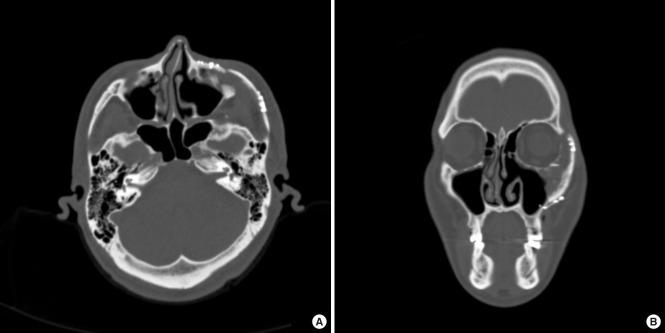

Fibrous dysplasia (FD) is a rare, benign bone disease with abnormal bone maturation and fibroblastic proliferation. Optimal treatment of zone 1 craniofacial FD is radical resection and reconstruction. To achieve of structural, aesthetic, and functional goals, we use three-dimensionally designed calvarial bone graft for reconstruction of zygomatic defect after radical resection of FD. The authors used a rapid-prototyping model for simulation surgery for radical resection and immediate reconstruction. Donor site was selected from parietal bone reflect shape, contour, and size of defect. Then radical resection of lesion and immediate reconstruction was performed as planned. Outcomes were assessed using clinical photographs and computed tomography scans. Successful reconstruction after radical resection was achieved by three-dimensional calvarial bone graft without complications. After a 12-month follow-up, sufficient bone thickness and symmetric soft tissue contour was well-maintained. By considering three-dimensional configuration of zygomaticomaxillary complex, the authors achieved satisfactory structural, aesthetic and functional outcomes without complications.

骨纤维异常增殖症(FD)是一种罕见的良性骨病,伴有异常的骨成熟和成纤维细胞增殖。颅面部1区FD的最佳治疗方法是根治性切除和重建。为了实现结构、美学和功能目标,我们使用三维设计的颅骨移植来重建FD根治性切除后的颧骨缺损。作者使用快速成型模型进行根治性切除和即刻重建的模拟手术。供骨部位选自顶骨,以反映缺损的形状、轮廓和大小。然后按计划进行病变的根治性切除和即刻重建。使用临床照片和计算机断层扫描评估结果。通过三维颅骨移植成功实现了根治性切除后的重建,且无并发症。经过12个月的随访,充分的骨厚度和对称的软组织轮廓得到了良好维持。通过考虑颧骨上颌复合体的三维结构,作者获得了满意的结构、美学和功能效果,且无并发症。